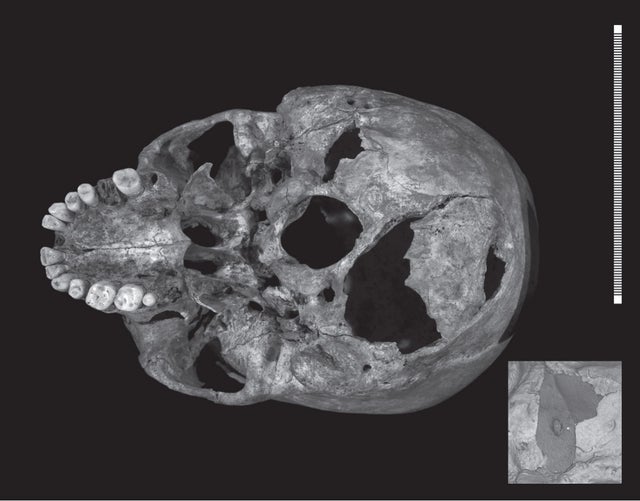

According to the findings outlined in the new study, the king sustained a total of 11 wounds at or near the time of his death at the Battle of Bosworth Field on August 22, 1485. Nine of the injuries were inflicted to the skull, which suggests that he had removed or lost his helmet. Two other wounds were found elsewhere on the body.

The investigators conclude that three of the injuries -- two inflicted to the inferior aspect, or underside, of the king's skull and one to his pelvis -- could have potentially caused death quickly. However, they detected signs that the pelvis injury may have occurred after the king was already dead, and therefore believe the other two injuries likely caused his death.

The fatal wounds to his skull were caused by "a large sharp force trauma possibly from a sword or staff weapon, such as a halberd or bill, and a penetrating injury from the tip of an edged weapon," study author Guy Rutty, of the East Midlands Pathology Unit at the University of Leicester, said in a statement. "Richard's head injuries are consistent with some near-contemporary accounts of the battle, which suggest that Richard abandoned his horse after it became stuck in a mire and was killed while fighting his enemies."

The researchers did not find any indications of defensive wounds to the king's arms and hands, which suggests that Richard was still wearing armor -- except for his helmet -- during his final moments.